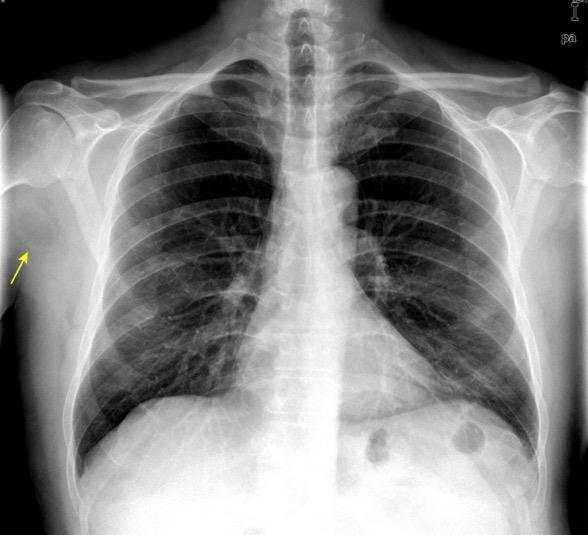

48 MASAS. LIPOMA SUBPECTORAL

Densidad similar al músculo con estriaciones internas de grasa

Hallazgo incidental . Región infraescapular 2% de TC del tórax. Bilateral 60%.

Burt AM et al. Imaging review of lipomatous musculoskeletal lesions. SICOT J2017/ Murphey MD et al. From the archives of the AFIP: benign musculoskeletal lipomatous lesions. Radiographics. 2004

50% de los tumores de partes blandas.

Predilección varones en lipomas profundos

30% “hereditarios”

Isointenso con grasa subcutánea